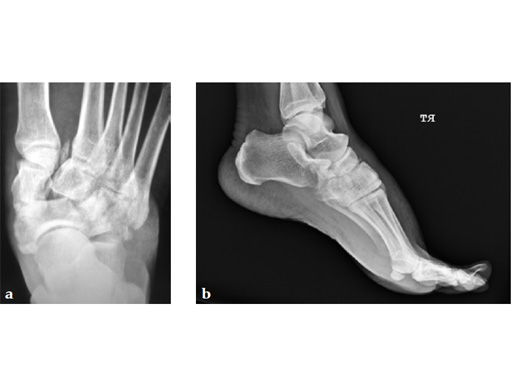

After 4 months the patient presented for a second opinion. His complaint was pain to the lateral column and subtalar joint. The preoperative lateral x-ray is notable for a malunited talar neck fracture with subluxation of the subtalar joint. The disproportion of the medial and lateral columns and a cavovarus position of the foot are seen on both the AP and lateral views. The degenerative changes at both the talonavicular and subtalar joints are significant.

The patient was treated with arthrodesis of the talonavicular and subtalar joints. The compression/ distraction device was used to restore the length of the medial column. The articular surface of the subtalar joint was prepared arthroscopically. The talonavicular joint was debrided then packed with a tricalcium matrix. Length was maintained using a locking X-plate. The subtalar joint was then fixed with a 6.5 mm headless compression screw.

The patient returned to work 3 months after surgery. He wears an ankle brace when on uneven surfaces. His lateral column and subtalar pain have resolved.